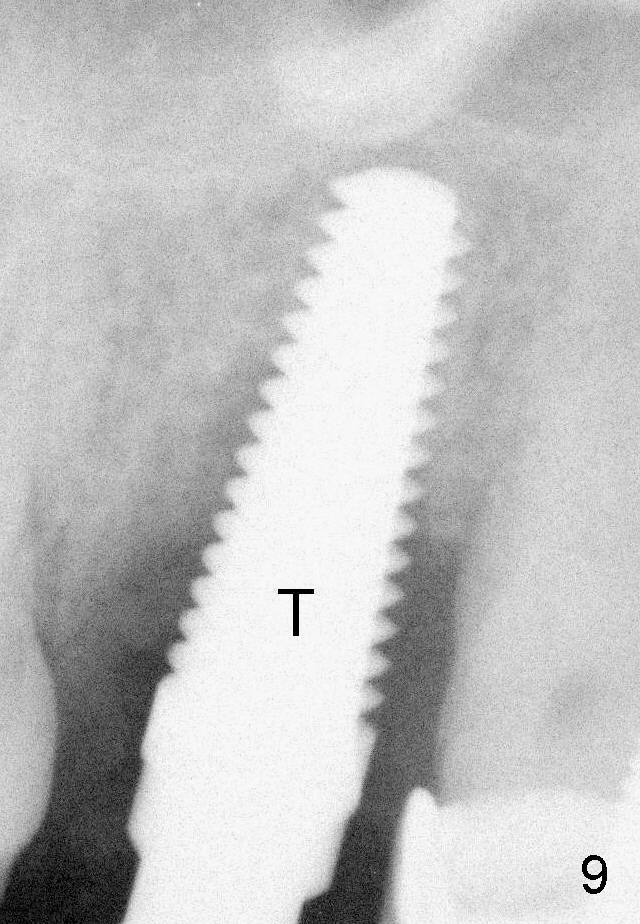

Fig.9: Tap (T) 5x17 mm, 14mm deep.